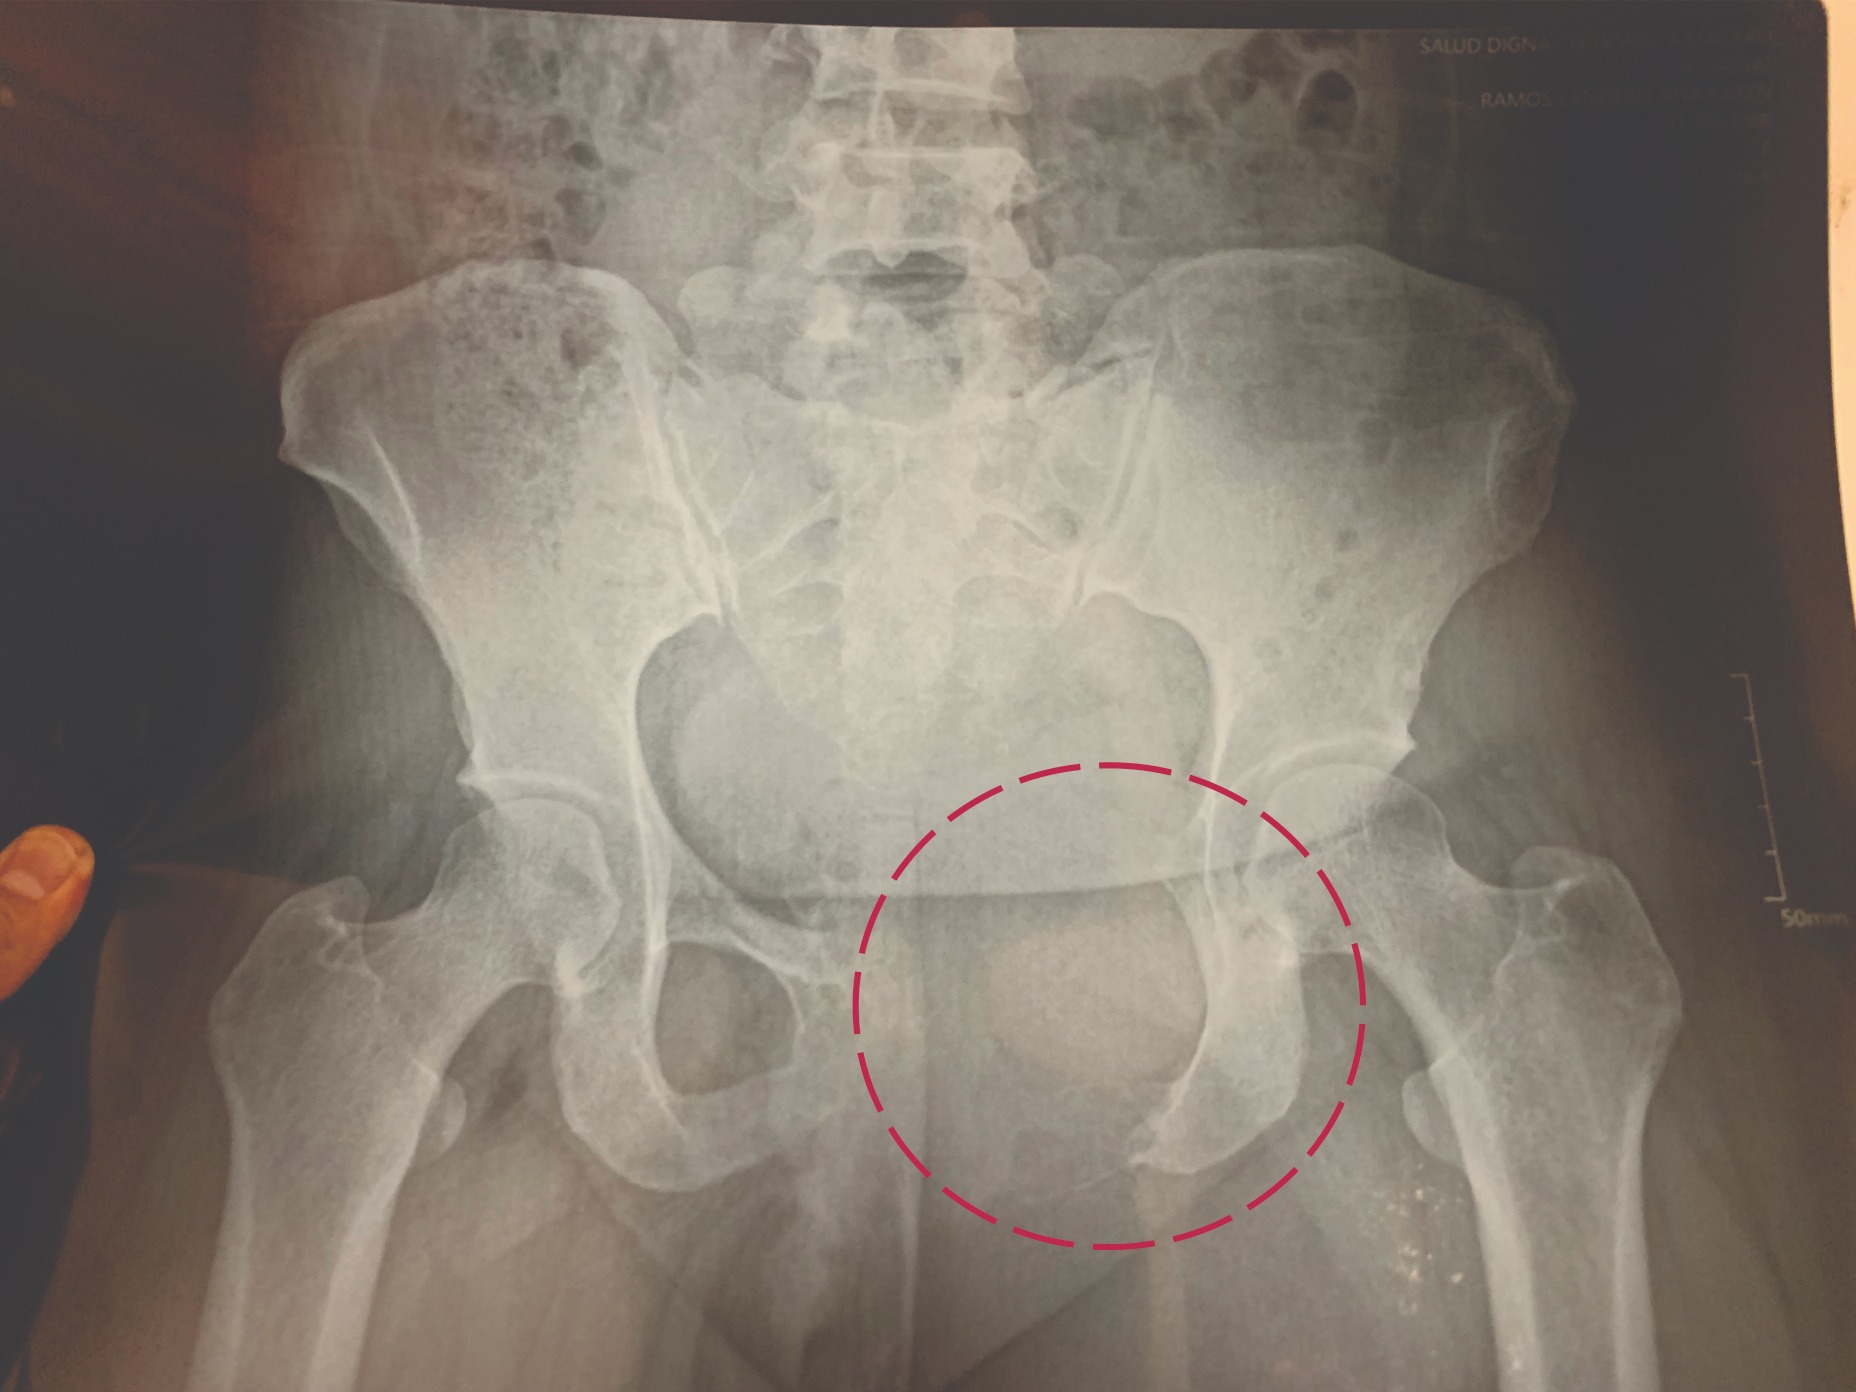

Fui diagnosticada con un TUMOR ÓSEO DE CÉLULAS GIGANTES (TCG) en la pelvis izquierda. A pesar de que es un tumor benigno, se comporta como uno maligno o peor aún, ya que avanza con rapidez y actualmente ya destruyó parte de la pelvis y sigue afectando otros órganos.

En Enero de 2025 fui aceptada en el Instituto Nacional de Cancerología INCAN en CDMX, donde empecé a recibir tratamiento con el medicamento Denosumab, pero mi tumor no respondió favorablemente ya que es muy grande de 18 cm y sigue creciendo y dañando. Los Doctores me proponen un procedimiento llamado CRIOABLACIÓN, el cual congela el tumor a muy bajas temperaturas y poder quitarlo con menor riesgo, y se requieren de varias cirugías.